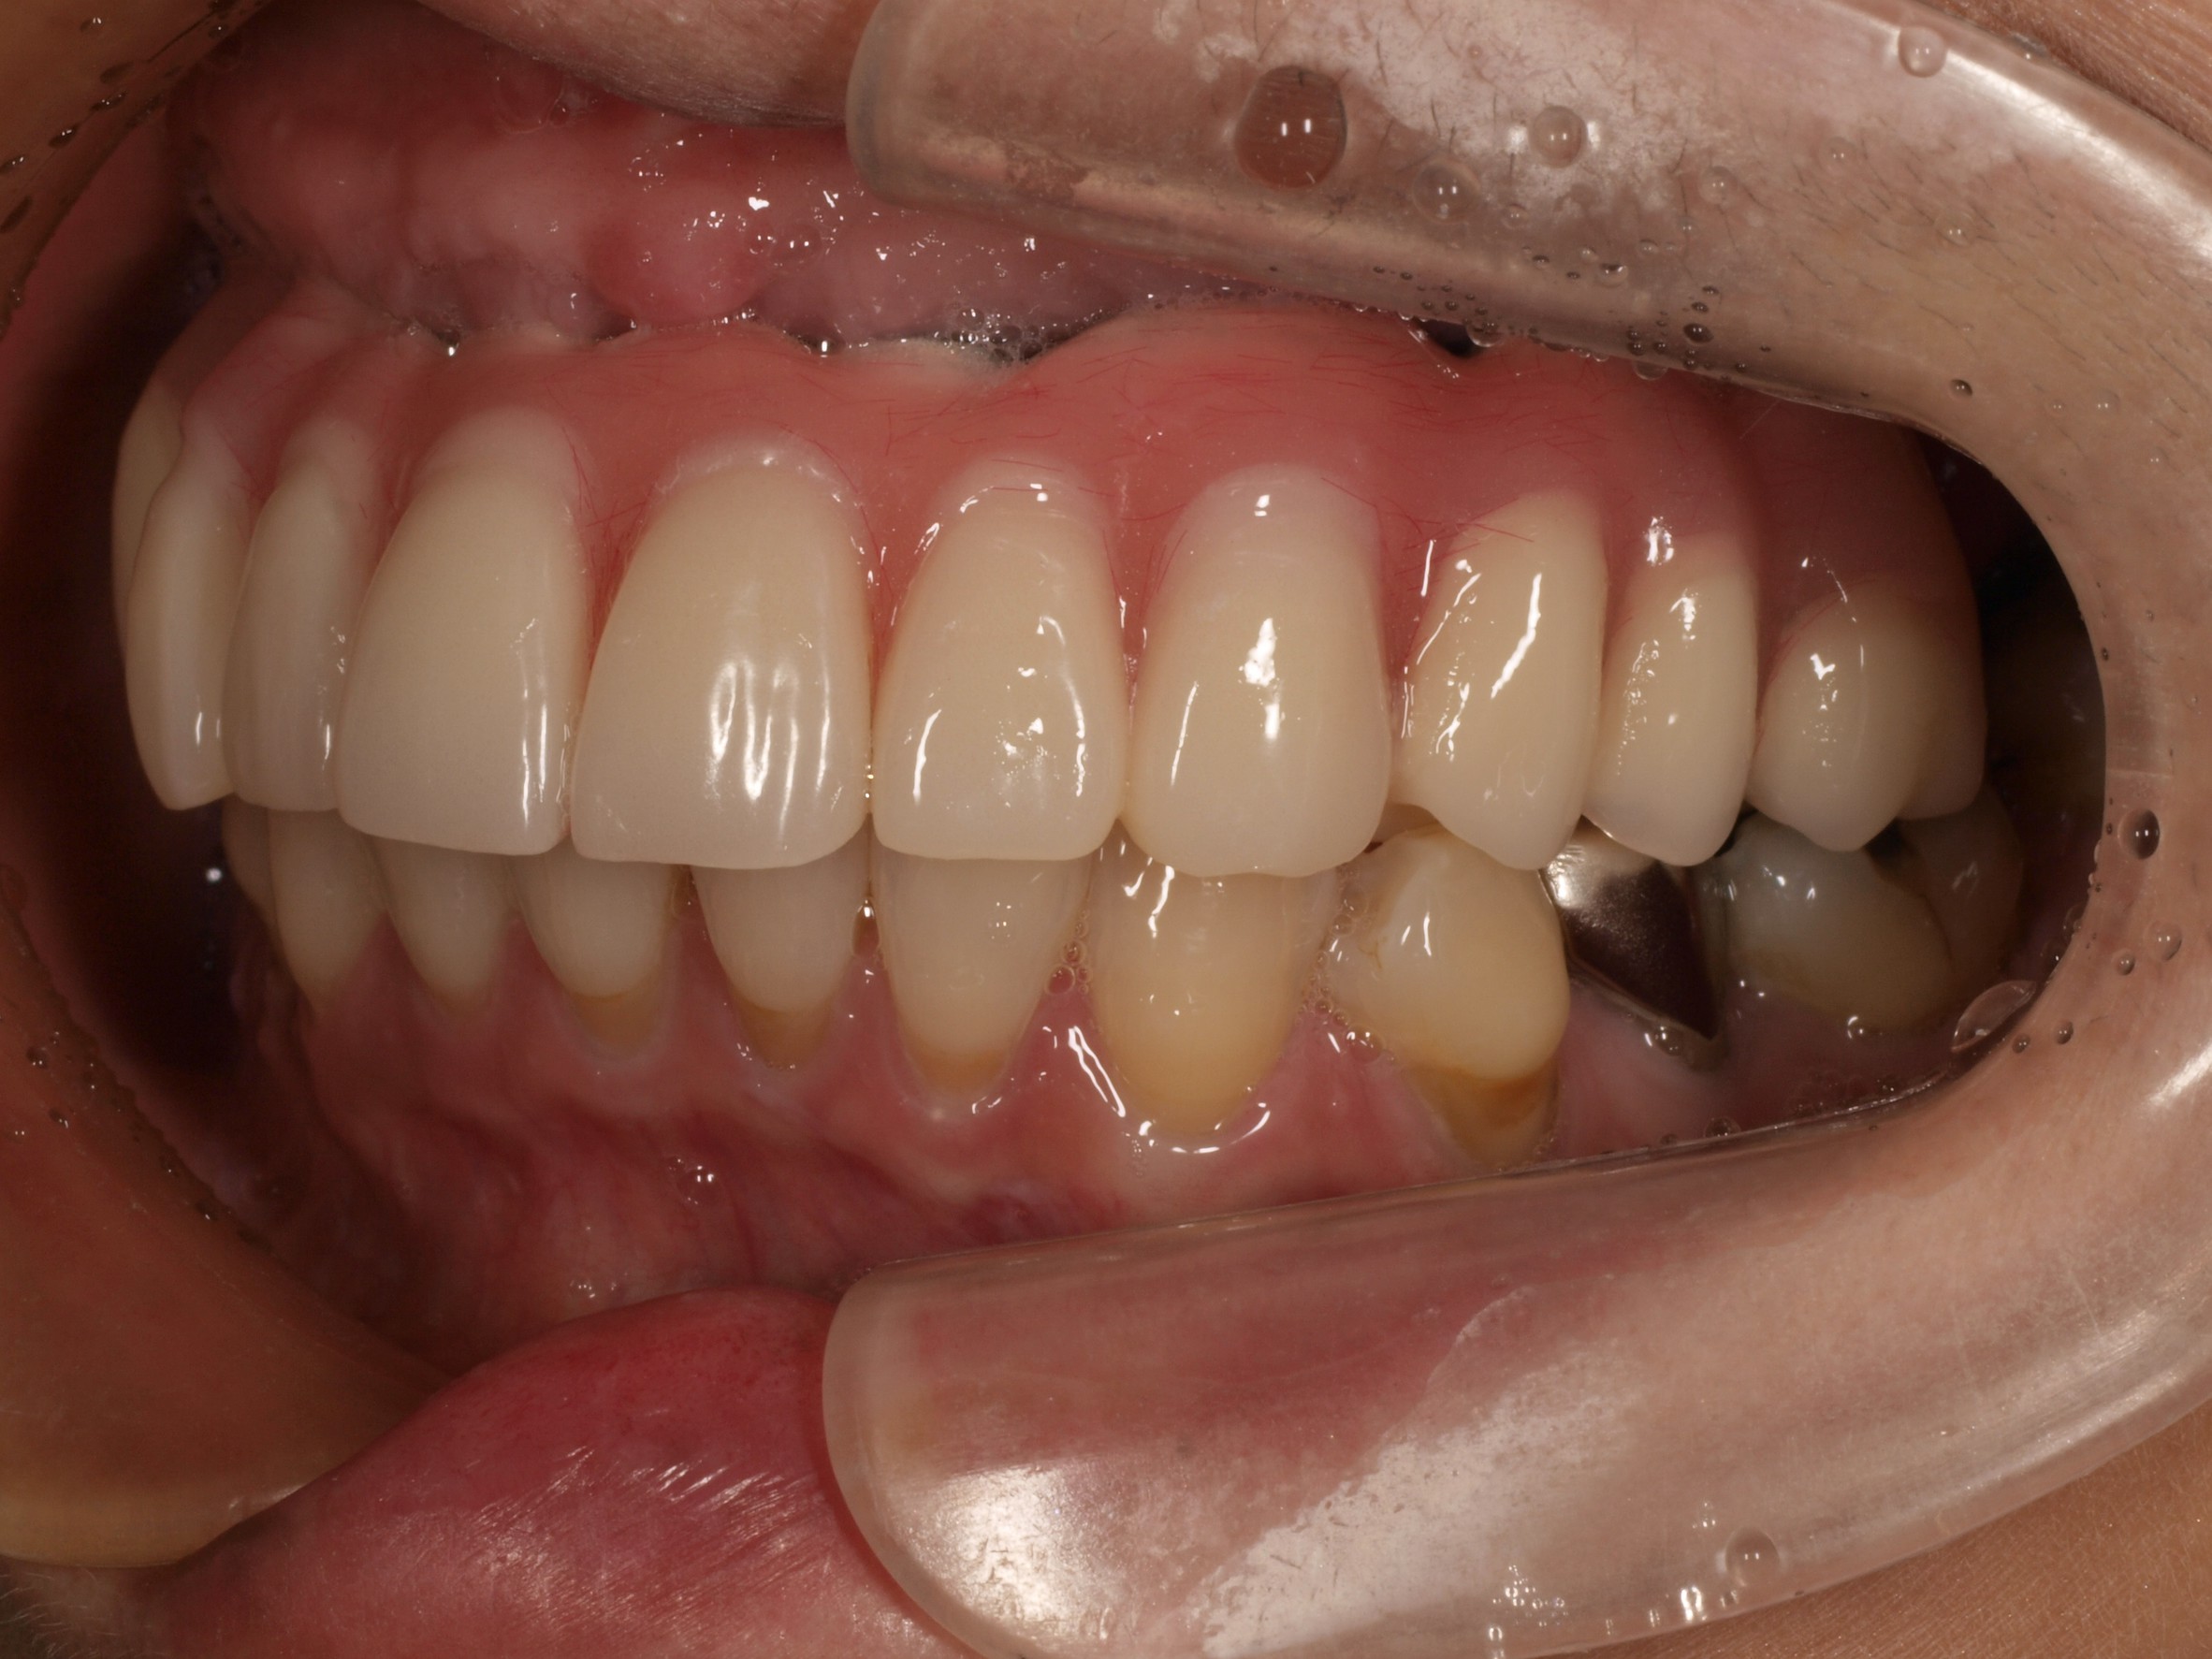

症例紹介

- 主訴

- 入れ歯が合わない。食べにくい。人生を豊かにしたい。

- 処置内容

- 上顎4本で12歯(オールオン4)、下顎4本5歯。

上下抜歯即時埋入、即時荷重(手術当日にインプラントの上に仮歯装着)

- 治療費用

- 上顎:約290万(税込)、下顎:約210万円(税込)

- 治療期間・通院回数

- 上顎:9か月/9回

下顎:6か月/7回

- リスク

- 術後の腫れ、痛み(ピークは3日後、1週間で軽減)

上部構造物、仮歯の破折、人工歯根脱落リスクがあります